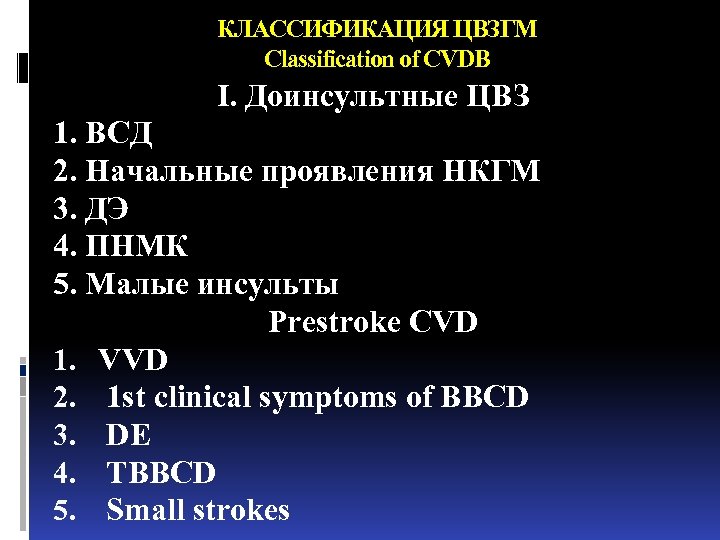

КЛАССИФИКАЦИЯ ЦВЗГМ Classification of CVDB I. Доинсультные ЦВЗ 1. ВСД 2. Начальные проявления НКГМ 3. ДЭ 4. ПНМК 5. Малые инсульты Prestroke CVD 1. VVD 2. 1 st clinical symptoms of BBCD 3. DE 4. TBBCD 5. Small strokes

КЛАССИФИКАЦИЯ ЦВЗГМ Classification of CVDB I. Доинсультные ЦВЗ 1. ВСД 2. Начальные проявления НКГМ 3. ДЭ 4. ПНМК 5. Малые инсульты Prestroke CVD 1. VVD 2. 1 st clinical symptoms of BBCD 3. DE 4. TBBCD 5. Small strokes